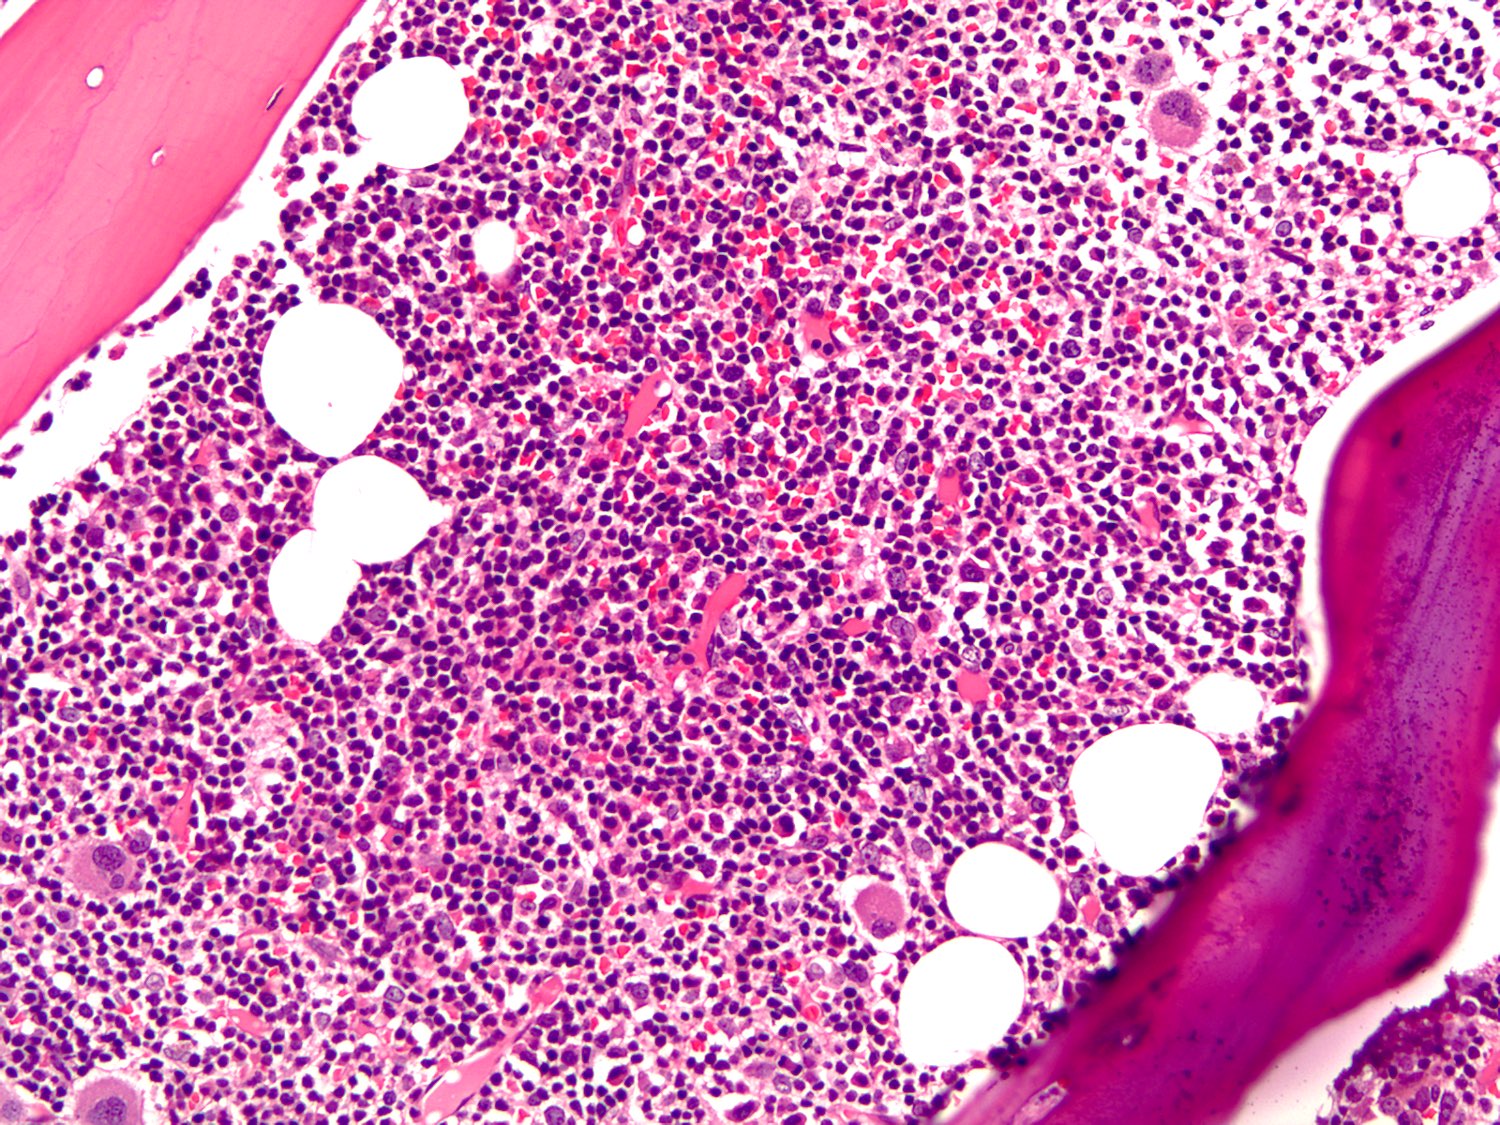

Microscopic (histologic) description

- Bone marrow (Arch Pathol Lab Med 2013;137:580)

- Core biopsy (Am J Surg Pathol 2005;29:1549, Am J Clin Pathol 2015;143:797)

- Most common pattern is the combination of paratrabecular and nonparatrabecular lymphoid nodules

- Less common patterns include paratrabecular or intrasinusoidal with or without interstitial infiltrate

- Pseudointranuclear (Dutcher bodies) and intracytoplasmic inclusions (Russell bodies) are most prominent on core biopsy section

- Amyloid deposition may be present within vessel walls or interstitial deposits

Microscopic (histologic) images

Contributed by Ling Zhang, M.D.

- Core biopsy and cell clot: The bone marrow core biopsy includes normal appearing trabecular bone and marrow, adequate for morphologic evaluation. The marrow cellularity is very high, up to 95%. Megakaryocytes are essentially normal in number with normal morphology. Myeloid and erythroid precursors are markedly decreased in number. The marrow is diffusely infiltrated by atypical lymphocytes, accounting for approximately 80% of total cellularity, a small subset of which shows plasmacytoid differentiation. Mature plasma cells are identified. Iron stain shows adequate stainable storage iron. Reticulin stain highlights mild reticulin fibrosis. The clot section contains a few small cellular particles including predominantly atypical lymphoid cells, with findings similar to the core biopsy.

- Immunohistochemical study: Immunohistochemical stains and in situ hybridization stains are performed on the core biopsy with adequate controls. CD20 and PAX5 highlight a diffuse infiltration of neoplastic B cells, occupying 80% of total cellularity. CD3 highlights scattered interstitial T lymphocytes, ranging from 2% to 5%. CD138 highlights scattered plasma cells, focally forming small clusters, accounting for approximately 5% of the total cells. By in situ hybridization (ISH), the plasma cells are positive for kappa light chain and negative for lambda light chain.